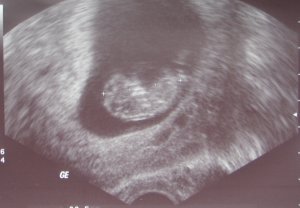

A saját képemet is nekem szentelem, hogy tudjad ki miatt idegesíted magad feleslegesen. Szóval megjártam a dokit, igazán csak most merem beleélni a terhességbe magam, hogy van kihez kötni a dolgot. Már én is terhesnaciba nyomulok nagy büszkén. :)

Szóval csak úgy kutyafuttában megnézte a doki, minden a helyén, placenta elöl tapad, a baba szíve ver, korának megfelelö méretü (ülömagasság olyan 3 cm). Lecsapoltak a vércsoportösszeférhetetlenség miatt ill. próbáltak egy toxoplazma-tesztre is rávenni, amire két éve is hiába próbáltak.

Legközelebb 3 hét múlva megyek. Nem lesz genetikai uh, azt mondta a doki, hogy nincs semmi feltünö, a teszt se 100%-osan biztos, mire én kiegészítettem, hogy a triszóma csak egyike a sok rossz kromoszómarendellenességnek, ami becsúszhat, és csak ezután néznek, a többi még lehet, akkor meg minek a felhajtás. Olyan ez, mint a Kinderschokolade meglepetéstojás, sose tudod mi van belül, de akármi is az, örülni fogsz neki. Reméljük a legjobbakat. A baba alighanem éppen aludt, mert nem kalimpált. Fazonra más, mint az elödjei, talán mert aludt.

Na és akkor a kép:

Kép

Képeket még nem tettem fel a gmailre, igyekszem pótolni a hiányt.